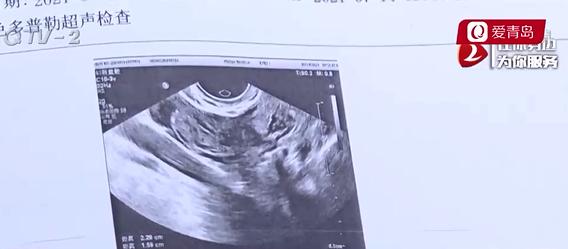

朱女士:我來醫(yī)院做了檢查,然后跟我說是異位妊娠和早孕,然后給我反復(fù)做B超很多次,跟我說是宮外孕的可能性比較大,然后就給我做了手術(shù)了。

圖片     當(dāng)天晚上,朱女士就到了西海岸人民醫(yī)院。根據(jù)醫(yī)院的診斷首先懷疑是異位妊娠,如果不抓緊做手術(shù)會危及到生命。7月14號,朱女士進(jìn)行了手術(shù)?墒侵炫空f,手術(shù)之后的后果讓她始料未及。

朱女士:7月14號做的手術(shù),(醫(yī)生)做完手術(shù)跟我說,宮外沒有找到孩子。在術(shù)中給我做了診斷性刮宮,給我做了刮宮術(shù),也就是說這個孩子應(yīng)該是在宮內(nèi)的,然后給我做了刮宮術(shù),就這么把孩子給我流掉了

西海岸新區(qū)人民醫(yī)院 婦科門診 徐主任:當(dāng)時查了個血是顯示懷孕,但是宮內(nèi)宮外并不確定,做了超聲然后懷疑里面有出血,但是出血還沒有那么多,就是在子宮外面有一個包塊,這種第一懷疑肯定是宮外孕,第二天上午確實是出血多了,病人肚子疼更明顯了,然后有手術(shù)指征,因為內(nèi)出血做的手術(shù),病人肚子里的出血不管是什么原因,宮外孕還是黃體破裂都需要手術(shù)的,為什么要刮宮,也就是說卵巢黃體破裂了,你不管哪個部位的妊娠,尤其是在早孕期間,沒有了黃體,他的結(jié)局都是一樣的,沒有生命的。

徐主任說,醫(yī)院不存在誤診的情況,起初給朱女士做手術(shù),是因為她體內(nèi)出血過多,雖然在手術(shù)中發(fā)現(xiàn)是黃體破裂,并不是宮外孕,但因為黃體破裂,孩子在宮內(nèi)也無法保住,所以才做了刮宮術(shù)。而且,徐主任表示,他們這么做也是征得了朱女士的同意。